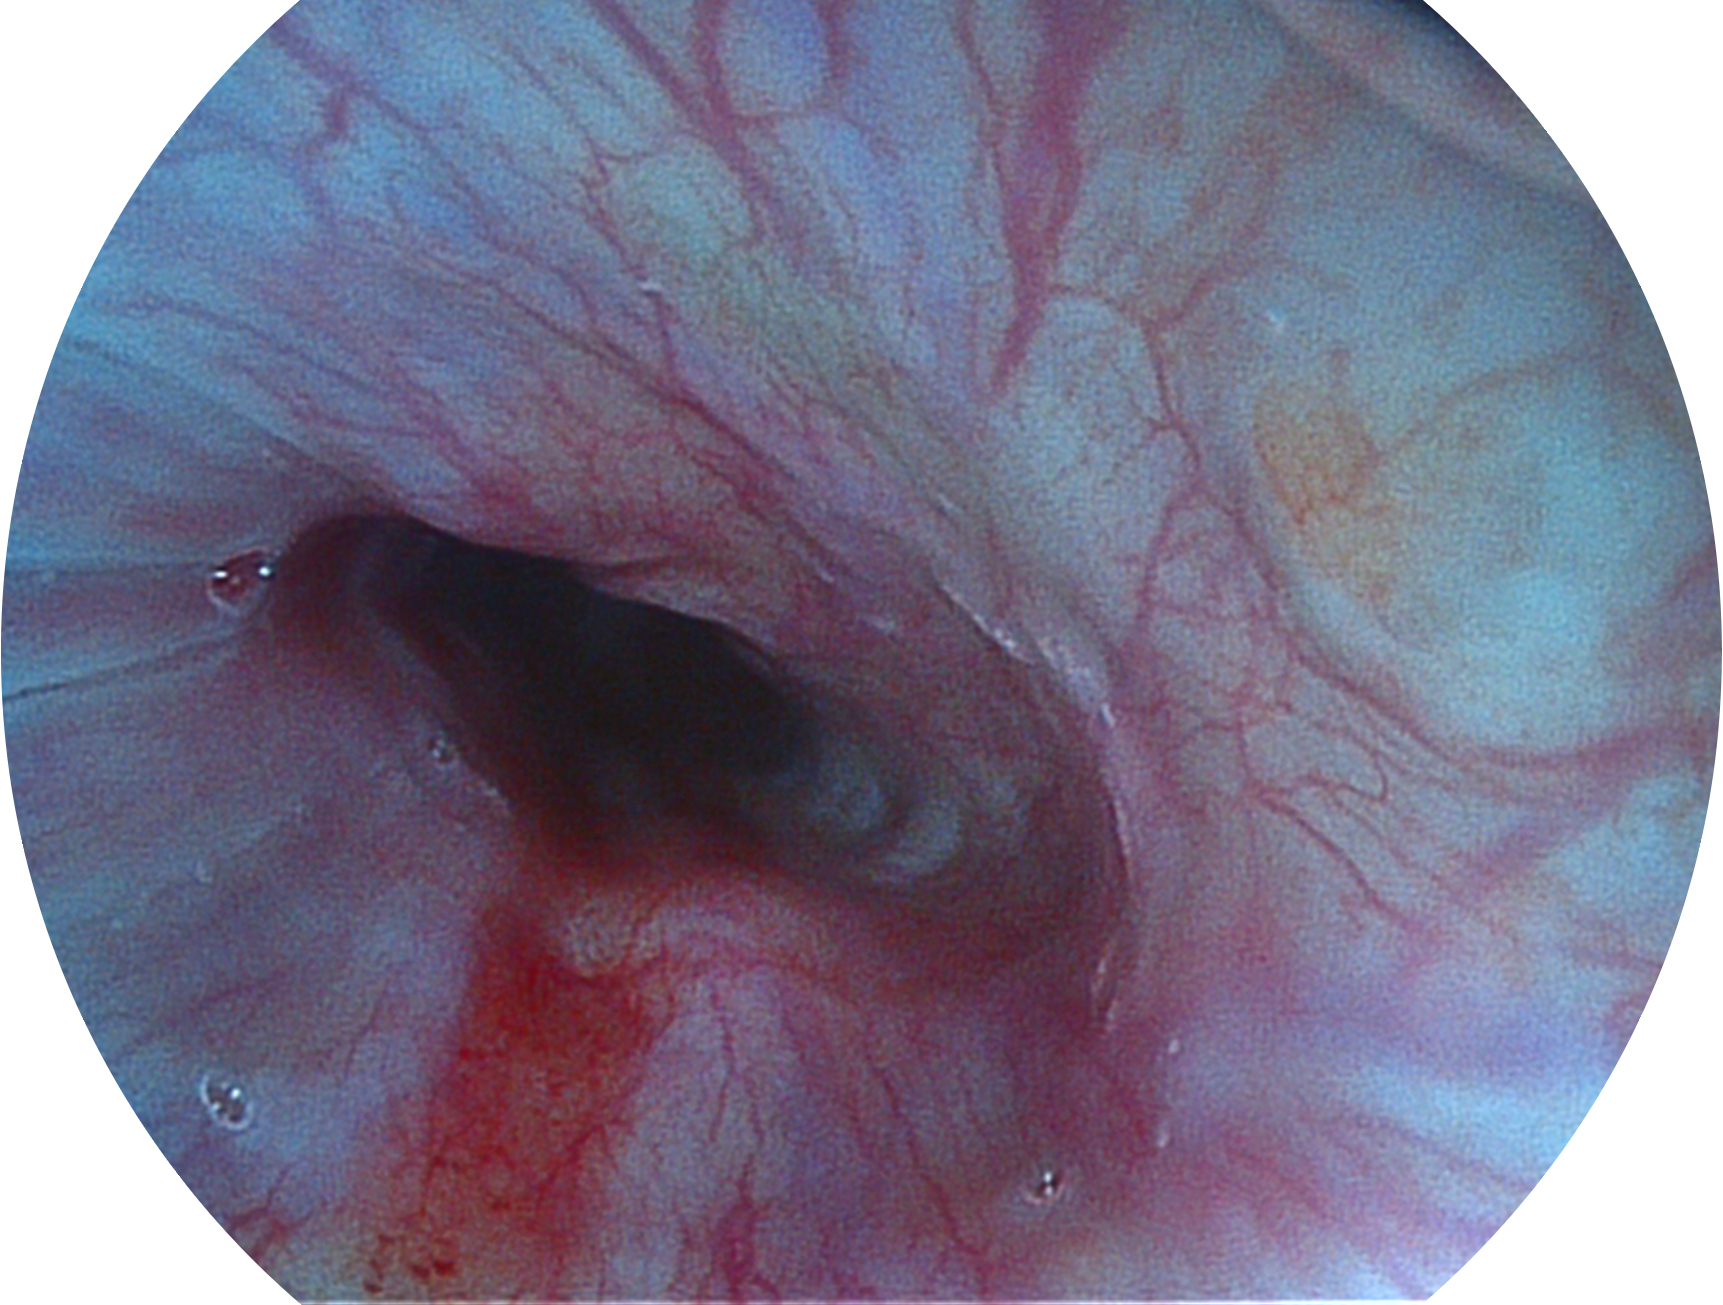

MILE米乐集团官网新开发的内镜染色技术,主要是基于多波长LED 光源的开发,VLS-55Q 四波长LED 光源是由四个不同颜色的LED光按照相应照明模式所规定的特定发光比例进行合束后形成,合束后形成的照明光的光谱由红光、绿光、蓝光及蓝紫光这四个不同的波段范围构成。具有更高光谱自由度,通过光谱比例的控制,实现了聚谱成像技术,英文全称为“Spectral Focused Imaging, SFI”,缩写为“SFI”和光电复合染色成像技术,英文全称为“Versatile Intelligent Staining Technology, VIST”,缩写为“VIST”。